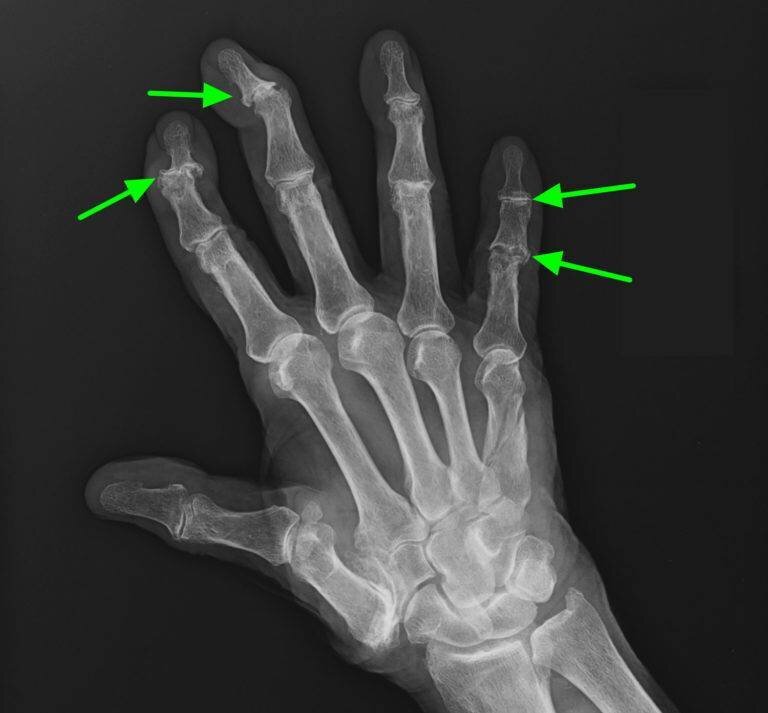

🟢 Рентгенография - самый простой и достоверный метод обнаружения сужения суставной щели и костных выростов (остеофитов).